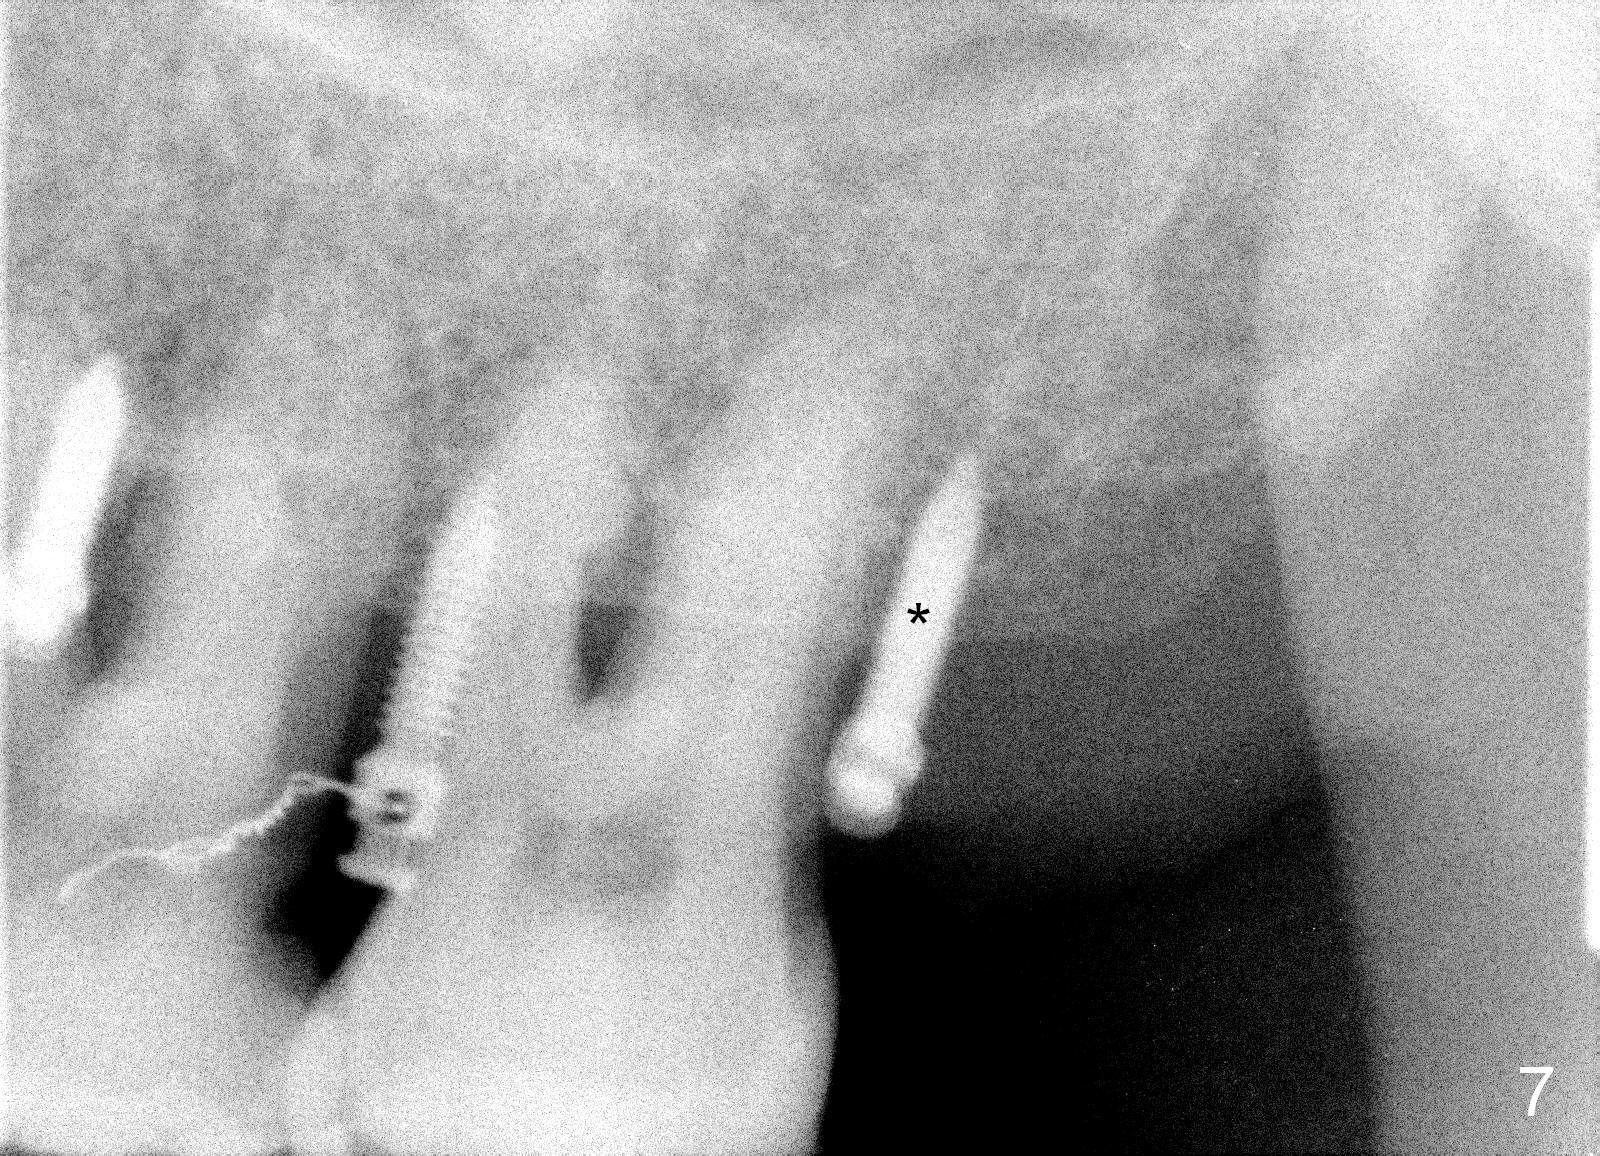

A 41-year-old man has chronic periodontits with bruxism. The teeth #14 and 15 are supraerupted (Fig.1 arrows) with furcal lesion (Fig.2 (CT) *). These 2 molars have guarded to poor prognosis. Due to insurance benefit limitation, we plan to save them temporarily with periodontal surgery so that bone loss would not get worse when the teeth are being intruded. After opposing implant placement (Fig.3), flaps are raised to remove calculus and granulation tissue (Fig.4, no bone graft). Twenty days later, three mini-implants are placed (Fig.5,6). The implant distopalatal to #15 is loose nearly 2 months postop (Fig.7 *) and retightened. The following month the same implant is placed higher for stability (Fig.8). The Intrusion takes <5.5 months (Fig.9,10).